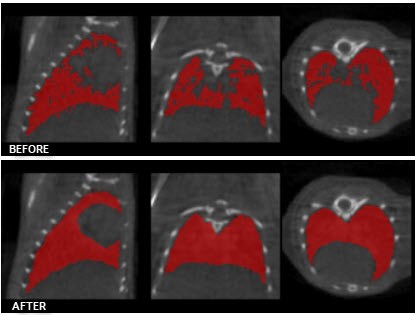

Low-pass Smoothing

Use the Low-pass Smoothing filter to remove jagged surfaces from manually created ROIs. The amount of smoothing can be controlled with the Low-pass radius parameter. Smaller radii will result in smoother ROIs.

Modal Smoothing

Use modal smoothing to reassign every voxel’s ROI value to the mode of the surrounding region specified by the given radius. The amount of smoothing can be controlled by the Mode Radius and Iterations parameters.